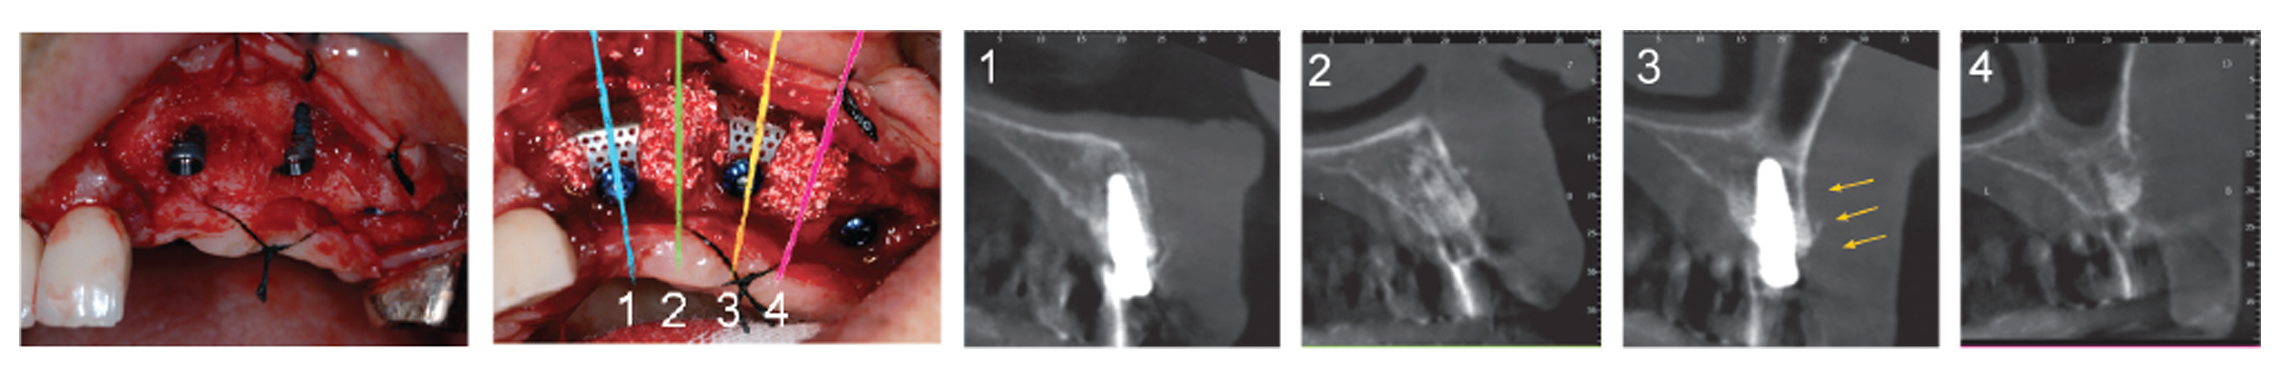

Any location, Any Size & Any Situation for GBR, i-Gen ensures regenerating minimum 2.5mm buccal bone. The regenerating of more than 2.5mm of buccal bone to minimize bone loss after GBR and maximize the life of implant.

Superior initial stability makes a perfect match for GBR using i-Gen membrane

AnyRidge can be placed in any ridge thanks to its knife thread. AnyRidge Knife thread has perfect stability in Regenerated bone.